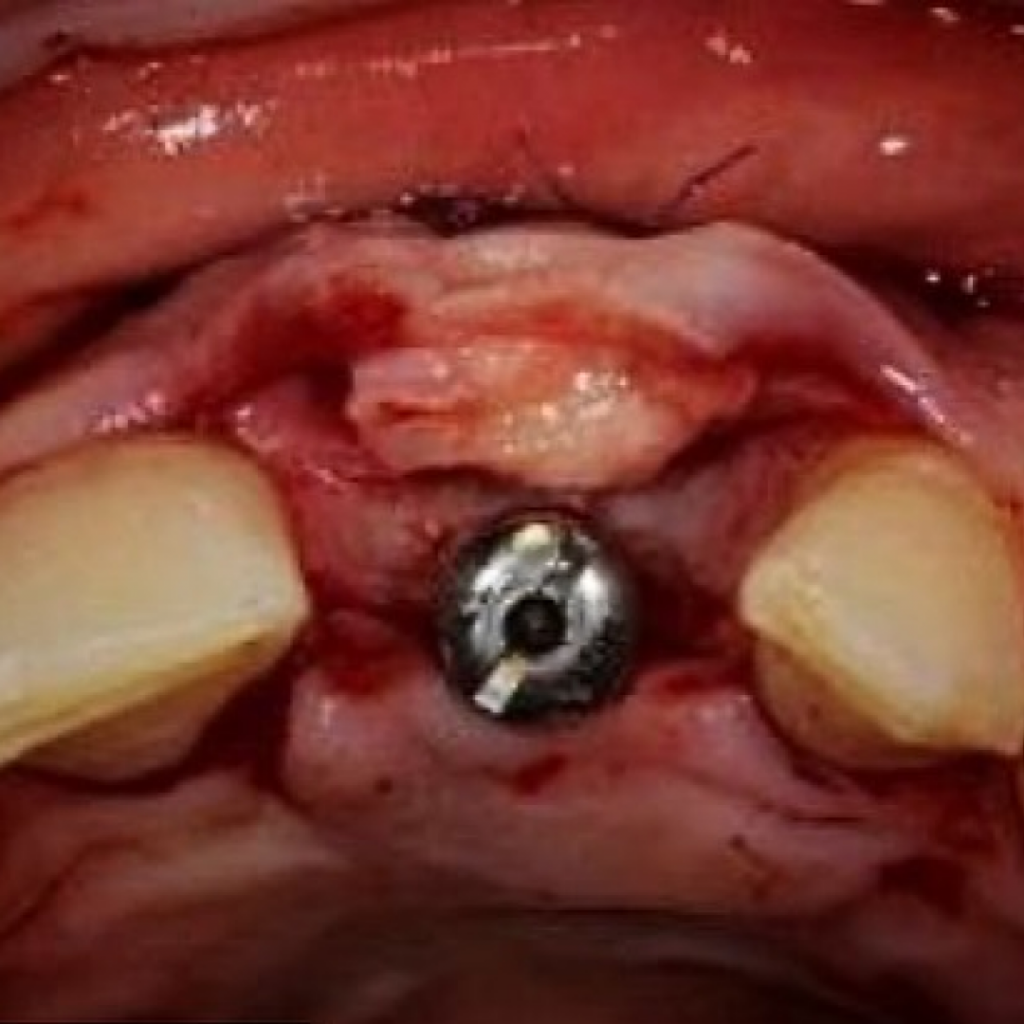

- Лечение: проведена дентальная имплантация AnyRidge в области зуба 2.1 с пластикой десны, а также установлена временная коронка.